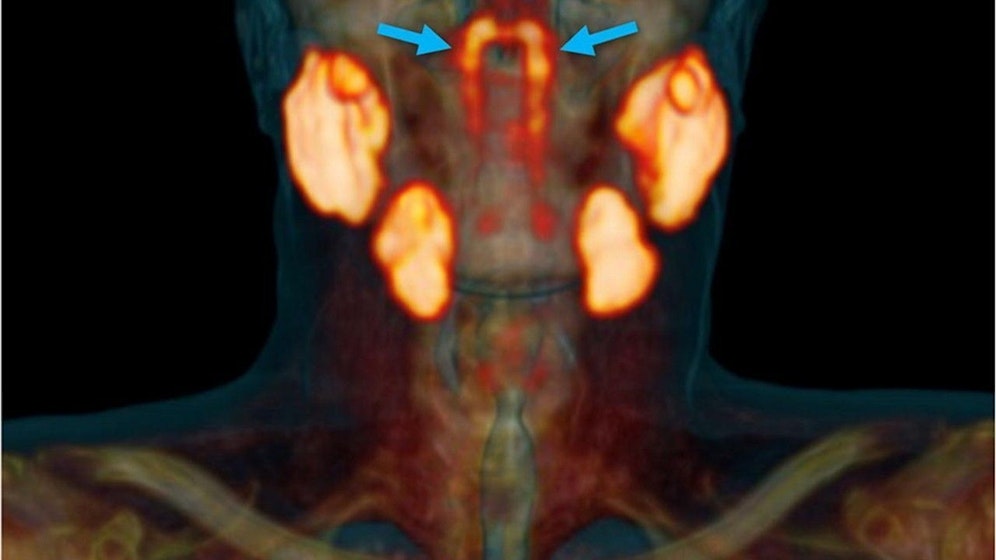

Wie Wissenschaftler durch Zufall herausfanden, befinden sich im Kopf noch unbekannte Speicheldrüsen. Ihre Ergebnisse veröffentlichten die Forscher in der Septemberausgabe des Branchenblatts "Radiotherapy and Oncology Journal". Die Strukturen ähneln jenen unterhalb der Zunge.

"Menschen haben drei Sätze großer Speicheldrüsen, aber nicht an dieser Stelle", erklärt Wouter Vogel vom Netherlandic Cancer Institute in einer Mitteilung. Sollte sich die Entdeckung behaupten, könnte sie Tumorpatienten Schmerzen ersparen.